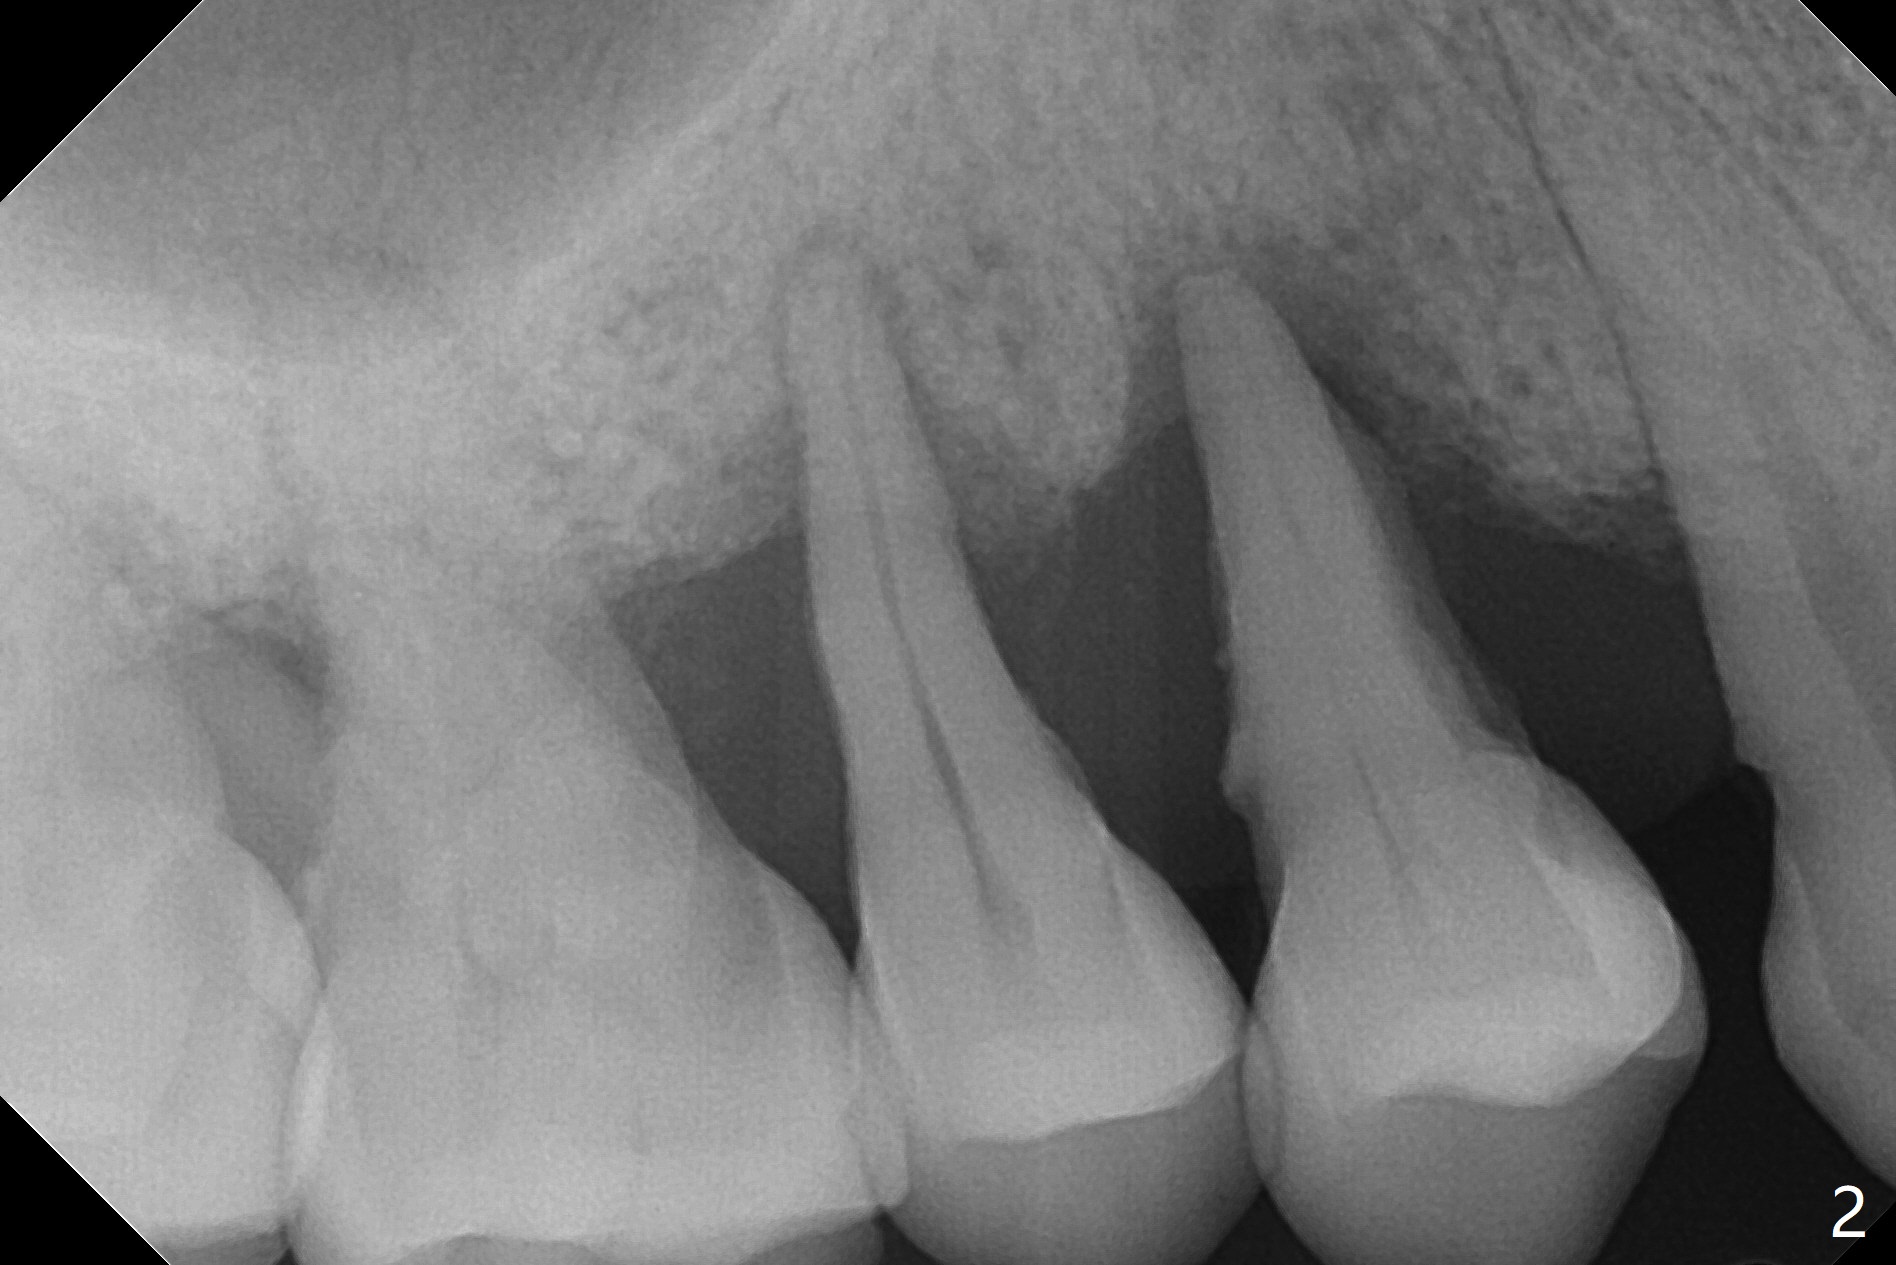

48岁女右上4,5骨质吸收松动五年里逐渐加重(图一,二),而牙龈退缩没那么明显。这两个后牙能同时拔除,种植吗?

一个月后病人要求4植牙。术前拍摄CT,决定植体大小,位置,准备SM和DIO/IS一段式植体,粘性骨块。